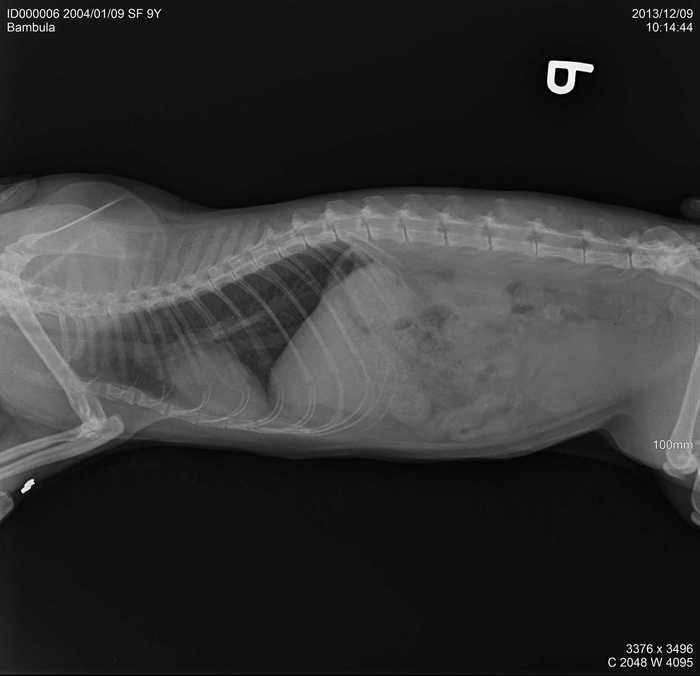

Úvod > Galerie > RTG snímky